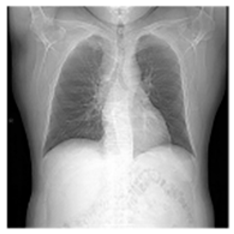

| Original Medical Images | |||||||

| Pair 1 | Pair 2 | Pair 3 | Pair 4 | ||||

![]() (1-9) PSNR = 44.14 | ![]() (1-10) PSNR = 41.90 | ![]() (1-11) PSNR = 40.09 | ![]() (1-12) PSNR = 41.41 | ![]() (1-13) PSNR = 42.24 | ![]() (1-14) PSNR = 40.35 | ![]() (1-15) PSNR = 40.79 | ![]() (1-16) PSNR = 40.84 |

| Shadow Images Produced by Using LSBs | |||||||

![]() (1-17) PSNR = 26.35 | ![]() (1-18) PSNR = 25.49 | ![]() (1-19) PSNR = 23.57 | ![]() (1-20) PSNR = 24.19 | ![]() (1-21) PSNR = 24.79 | ![]() (1-22) PSNR = 24.23 | ![]() (1-23) PSNR = 23.26 | ![]() (1-24) PSNR = 24.42 |

| Shadow Images Produced by Using Middle Bits | |||||||

![]() (1-25) PSNR = 18.97 | ![]() (1-26) PSNR = 19.95 | ![]() (1-27) PSNR = 14.10 | ![]() (1-28) PSNR = 13.84 | ![]() (1-29) PSNR = 16.66 | ![]() (1-30) PSNR = 13.23 | ![]() (1-31) PSNR = 13.38 | ![]() (1-32) PSNR = 14.75 |

| Shadow Images Produced by Using MSBs | |||||||